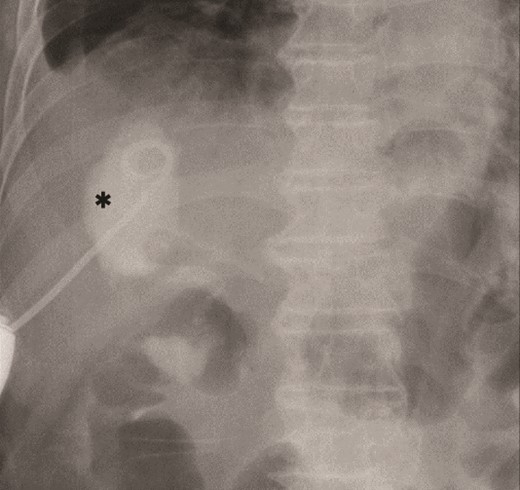

The amylase levels of drainage fluid and blood at postoperative day (POD) 1 (Ascites 6980 IU/dl, Serum 1123 IU/dl) and POD 3 (Ascites 673 IU/dl, Serum 487 IU/dl) revealed pancreatic fistula based on the criteria of International Study Group of Pancreatic Fistula [2]. After that, their results improved, and fluoroscopy showed no stenosis and leakage. Therefore, we removed all drains at POD 8, however the following day, the patient developed high fever. Plain CT revealed intraperitoneal fluid around subdiaphragmatic and duodenal stump (Fig. 3). We inserted a pig-tail drainage tube to the subdiaphragmatic space (Fig. 4). Since biliary fluid was discharged through the tube, we suspected duodenal leakage and started infusion of somatostatin analogs and antibiotics. At POD 13, the patient complained of whole abdominal pain with peritoneal signs. As the patient became hemodynamically unstable, we performed emergent laparotomy to lavage and insert multiple drainage tubes. Two perforation pinholes were identified in the anterior wall of the duodenum, near the stump. We resected the vulnerable duodenal stump including the perforation site and closed by Gambee’s method with unabsorbable 4–0 proline (Fig. 5). We inserted multiple drainage tubes (Fig. 6a): a C-tube from the cystic duct into the common bile duct to separate biliary juice and pancreatic juice, a dual drainage tube around the duodenal stump with continuous suction (Fig. 6b), a simple intraluminal drainage tube via the duodenum near the stump through a new skin incision on the left side of the abdomen for duodenal decompression, and a drainage tube into the rectovesical pouch. After the reoperation, we irrigated the cavity around the duodenal stump through each drain with saline. Since the contrast agent did not flow into the duodenum and the cavity around the duodenal stump gradually got smaller (Fig. 7), oral intake of fluid diet was initiated at POD 37. However, fistulography at POD 44 showed that the fistula of duodenal stump had relapsed (Fig. 8). Although we considered performing second reoperation for duodenal stump closure, due to the cavity around the duodenal stump was located, we continued conservative management and irrigation via drainage tubes. Fistulography demonstrated no leakage from the duodenal stump at POD 56, and the patient discharged at POD 59.

Primary drainage for duodenal fistula. As percutaneous approach, we inserted a pig-tail drainage tube to subdiaphragmatic space (asterisk) using X-ray fluoroscopy.